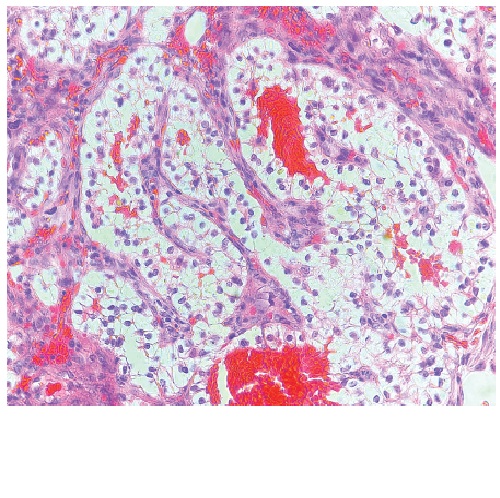

Primary Bilateral Ovarian Choriocarcinoma in a 33-year-old, G3P3(3003) Female

Sarah Lizette Aquino-Cafino, Jose Vicente Borja II, Al-Zamzam Abubakar

31-36

PDF

DOI:

https://doi.org/10.21141/PJP.2025.05